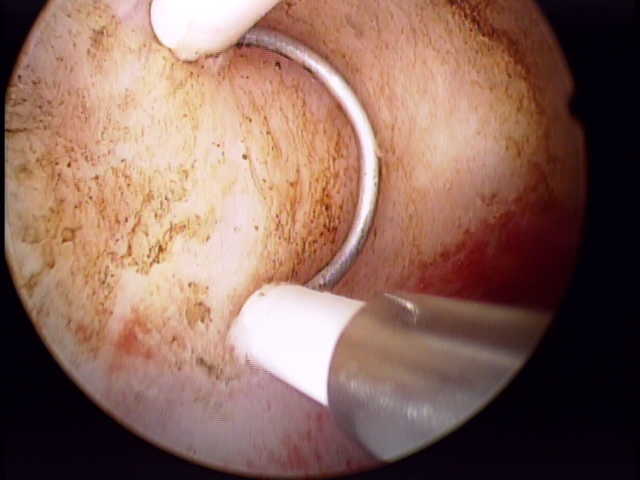

Durante o procedimento, a paciente permanece em posição ginecológica enquanto o ressectoscopio passa pela via vaginal e do colo do útero até o interior da cavidade uterina - sem incisões. Este aparelho contém uma lente óptica capaz de aumentar em até 20x a imagem - transmitida em tempo real para um monitor de vídeo - além de uma alça metálica que, através da função de corte e coagulação, possibilita a retirada da patologia a ser tratada.

Em geral, através da histeroscopia cirúrgica, miomas de até 05 centímetros podem ser retirados por completo, com todos os benefícios de um procedimento minimamente invasivo: sem cortes, em um único tempo cirúrgico e com rápida recuperação. Contudo, algumas pacientes podem ter particularidades antes e durante das cirurgias e mais de um tempo cirúrgico pode ser necessário.